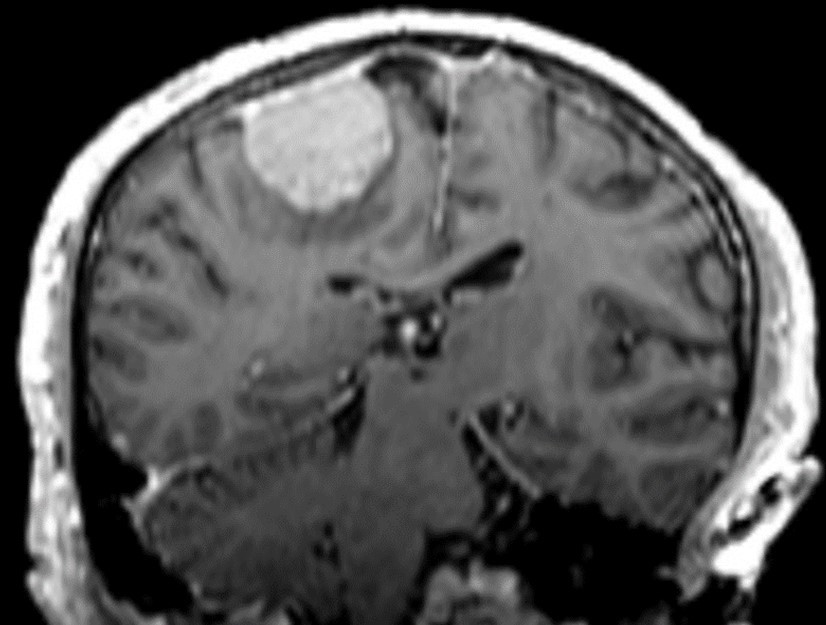

Treatment planning for LINAC-based radiosurgery has been performed by ERGO ++ (CMS, Elekta, UK) radiosurgery planning system. Optimal target coverage and normal tissue sparing has been achieved by using a single 360-degree arc, double 360-degree arcs, or five 180-degree arcs in radiosurgery planning. Synergy (Elekta, UK) LINAC available at our department has been used in delivery of treatment. Delineation of the target volume on planning CT and MR images has been optimized by selecting the appropriate windows and levels for radiosurgery planning. Sagittal and coronal images have been used in addition to the axial planning CT images to achieve accurate contouring of target volume and critical structures. Arc Modulation Optimization Algorithm (AMOA) has been utilized for optimization of target volume coverage and critical organ sparing. Figure 1 shows coronal CT image of a patient with atypical meningioma, and Figure 2 shows the corresponding coronal MR image of the same patient with atypical meningioma.

Figure 2.Corresponding coronal MR image of the same patient with atypical meningioma